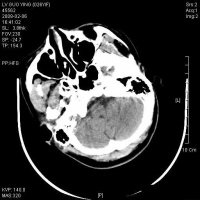

脑干含有大部分的脑神经核(除了嗅神经视神经),全身感觉、运动传导束,及呼吸循环中枢,脑干网状结构参与和维持意识清醒。故损伤后出现…… 1.意识障碍 原发性脑干损伤病人,伤后常立即发生昏迷,轻者对痛刺激可有反应,重者昏迷程度深,一切反射消失。如有昏迷

脑干损伤CT图

持续时间较长,很少出现中间清醒或中间好转期,应想到合并颅内血肿或其他原因导致的继发性脑干损伤。

8.CT扫描 是目前辅助诊断颅脑损伤的重要依据。能显示颅骨骨折、脑挫裂伤、颅内血肿、蛛网膜下腔出血、脑室出血、气颅、脑水肿或脑肿胀、脑池和脑室受压移位变形、中线结构移位等。病情变化时应行CT复查。

9.MRI 急性颅脑损伤患者通常不作MRI检查。但对病情稳定的弥漫性轴索损伤、大脑半球底部、脑干、局灶性挫裂伤灶和小出血灶、等密度亚急性颅内血肿等,MRI常优于CT扫描。

2.颅脑CT、MRI扫描 原发性脑干损伤表现为脑干肿大,有点片状密度增高区,脚间池桥池四叠体池及第四脑室受压或闭塞。继发性脑疝的脑干损伤除显示继发性病变的征象外,还可见脑干受压扭曲向对侧移位,MRI可显示脑干内小出血灶与挫裂伤,由于不受骨性伪影影响,显示较CT清楚。